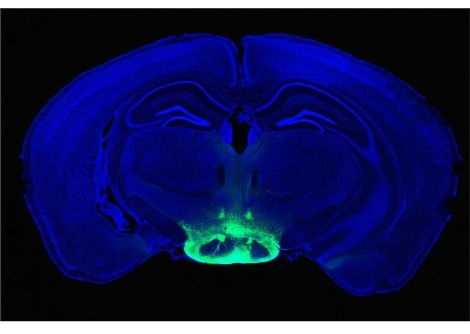

عرّض الباحثون الفئران للكحول أو دخان التبغ أو كليهما مرتين يوميًا لمدة 28 يومًا. قارن الباحثون أدمغة هذه الفئران بفئران لم تتلق أي عقار من العقاقير. وجد الباحثون أن تناول الكحول والتدخين معًا قد زاد من مستوى الأكسجين التفاعلي في منطقة في الدماغ تعرف بقرن آمون (Hippocampus) مقارنة بالحيوانات التي لم تتعرّض للعقاقير أو الفئران التي تعرضّت لدخان التبغ وحده. أدى الجمع بين الكحول والتدخين إلى زيادة مستويات السيتوكينات المضادة للالتهابات في جميع مناطق المخ التي شملتها الدراسة.

أظهرت الفئران التي تلقّت كلا العقارين مستويات منخفضة من عامل التغذية العصبية، وهو عامل نمو يساعد الخلايا العصبية الموجودة على البقاء ويحفز نمو خلايا جديدة، في منطقتي النواة المخططية striatum والقشرة الأماميّة frontal cortex.